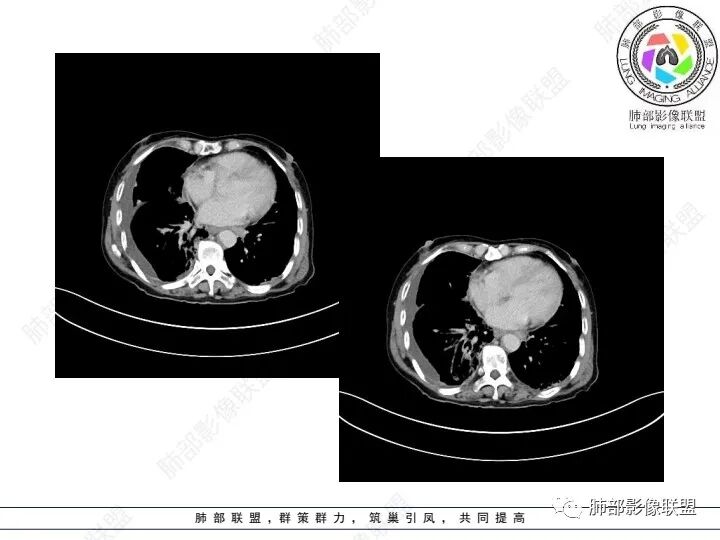

右肺下叶胸膜下不规则肿块,与肺门相连,不均匀强化,胸壁受侵,右肺内多发小结节,下叶血管束增粗,小叶间隔增厚,右肺门及纵膈多发淋肿大淋巴结,融合,右侧胸水,考虑腺癌转移

患者老年女性,腹痛、黑便4小时。查肿瘤结果CA125明显升高,余正常。胸部CT:双肺胸膜下间质性改变,右肺胸膜下多发结节灶,以右肺下叶为大,增强渐进性强化,内低密度灶。右肺门淋巴结肿大伴钙化,右中间支气管狭窄,右侧包裹性胸腔积液。综合考虑恶性,腺癌可能大。鉴别转移。

右肺下叶胸膜下肿块,密度不均,不均匀强化,胸膜栽赃,右肺多发小结节,右肺门及纵膈多发淋肿大淋巴结,下叶支气管受压变窄,右侧胸水,考虑恶性,腺癌转移。

右肺下叶占位,右肺下叶支气管狭窄,周围见软组织密度结节包饶,增强结节病灶强化不明显,右肺胸膜下见多个结节影,考虑恶性病变,低分化腺癌可能

老年女性,以消化道出血入院,右肺下叶靠近脊柱旁肿块,边缘毛糙,有栽赃,内有坏死,胸膜多发结节,右侧胸腔积液,同侧肺门纵隔多发肿大淋巴结,考虑恶性肿瘤可能,不知是一元还是二元,一元消化道肿瘤肺转移?或者二元肺部肿瘤胸膜转移,肿瘤标志物不是很高,考虑间皮瘤?淋巴瘤?

右下肺实变影,周围模糊,均匀强化,内可见低密度坏死,局部胸膜肥厚粘连,胸腔积液,纵隔淋巴结肿大,恶性肿瘤要首先排除。

老年女性,肺气肿背景。腹痛、便血入院。右肺下叶脊柱旁软组织肿块,强化不均匀,中心有坏死,纵隔及双侧肺门多发肿大淋巴结、有融合,右下支气管周围为主,包绕支气管生长,且管壁增厚伴环形钙化、狭窄,增强后有环形强化。右侧胸膜见结节灶,增强后明显强化;右侧胸腔积液。考虑:右下肺恶性肿瘤伴纵隔、肺门多发肿大淋巴结,胸膜转移,低分化腺癌?Ca125明显升高,老年女性 是否有妇科恶性肿瘤?黏液腺癌 肺内、纵隔转移?

右肺下叶胸膜下病灶,强化不均,右肺门淋巴结肿大,首先考虑恶性,肺原发肺癌可能,另外有胃肠道的症状,转移性不能除外,似乎有胸膜多发结节,胸腔积液呈包裏性,又有肺门区钙化,粘液腺癌转移不除外。

双肺间质性改变,右肺下叶支气管环形增厚,支气管变窄,周围见钙化影,右肺下叶软组织占位,明显的坏死,明显环形强化,两侧肺门及气管隆突下淋巴结肿大。右侧胸腔积液,肝脏周围少量腹腔积液,老年女性患者腹痛便血,Ca125明显增高。考虑1一元论:腹腔恶性肿瘤(胃肠道或卵巢来源)肺内及胸膜腹膜转移;2二元论:右下肺粘液表皮样癌/腺样囊性癌,腹腔胃肠道或卵巢来源肿瘤。

右肺下叶类圆形软组织密度影,纵隔及肺门多发肿大淋巴结、有融合,右下肺支气管壁增厚伴环形钙化、狭窄,右侧胸膜见结节灶,增强后均匀明显强化;右侧胸腔积液。考虑:右肺下叶肿瘤伴纵隔肺门、胸膜转移,考虑腺癌可能。

右肺下叶脊柱旁软组织肿块,外周强化,中心坏死,多发肿大淋巴结,右下支气管周围病灶环绕,密度不均,胸膜下多发结节包裹性胸腔积液。腹部症状。首先考虑结核的可能。。其次腺癌

老年女性,右肺下叶后基底段实性肿块,边缘强化明显,坏死,形态湖泊状,坏死轮廓不清,右肺门下方淋巴结肿大融合,包绕右肺下叶支气管血管束开口,右肺脏层及叶间胸膜多发转移强化结节,右侧胸腔积液,肺气肿背景,支持恶性,肺腺Ca,右肺下叶肿块经皮肺穿刺活检,另消化道岀血,Ca125值明里高,与肠Ca,补充腹部CT平扫及增强和肠镜检查,肠Ca右肺转移待排。

女,69,腹痛、便血4小时。CA125增高。胸部CT:肺气肿背景。右下叶不规则肿块影,处于外周气肿带与正常肺交界区,强化不均匀,中心有坏死;纵隔及肺门多发肿大淋巴结、融合,包绕支气管,部分钙化、环形强化;右下支气管周围管壁增厚伴环形钙化、狭窄。右侧胸膜多发结节灶,增强后明显强化,右侧胸腔积液。考虑恶性,右下肺腺Ca多发转移?转移瘤?鉴别TB、IgG4等。

右下肺肿块,其内坏死边界不清,边缘轻度强化,可见引流支气管,管壁增厚,冰冻肺门,内见斑点状钙化,中间支气管变窄呈针孔样,可见环状强化及血管浸蚀,右侧积液,间隔旁型肺气肿,慢阻肺背景,综和考虑腺并肺门纵隔及胸膜转移,纵隔内淋巴结环状强化,血管破坏显著,肿大淋巴结内多发钙化,引流支气管壁增厚,鉴别一下TB

1、老年男性,腹痛、便血就诊,既往有甲减病史,其余病史无特殊。

2、实验室检查CA125明显升高,其余肿瘤标志物无异常。

3、胸部增强CT示右肺下叶脊柱旁不规则软组织肿块,侵及壁层胸膜外,密度不均匀,不均匀强化,中心低密区可疑坏死,右侧胸腔积液、胸膜结节影或结节样增厚,增强扫描可见强化,右侧肺门及纵隔内可见淋巴结肿大、融合,右侧中尖段支气管及右肺下叶支气管受侵,管腔狭窄。

4、综上,老年男性,CA125升高,右肺下叶肿块侵犯胸壁,伴纵隔、右肺门及纵隔淋巴结肿大,右侧胸腔积液、胸膜增厚伴结节影,强化明显,应该为一较典型的肺癌伴肺胸膜腔及肺门纵隔淋巴结转移,尤其是肺腺癌。

几个细节值得留意:

1)由肺内侵及胸壁的块影,即提示其恶性生物学行为,也不为转移灶所常见。

2)右肺下叶肿块,右肺门及纵膈未见肿大淋巴结,符合肺癌迁徙途径。

3)转移瘤较少直接侵犯支气管。不是没有,如肾透明细胞癌转移或晚期无差别攻击,但总体较少。

4)转移灶多发但均限于右侧胸腔内,一般不符合远道而来的“双侧”。无论该患者有无腹腔或其他部位原发病灶。